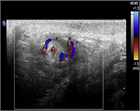

1. 急性陰嚢症の患者に対して、画像診断はカラードプラー超音波検査が簡便かつ低侵襲で有効である。最も正確に精巣捻転症(精索捻転症)かどうか評価することができるのは手術治療だが、超音波検査(カラードプラーを含む)によって、かなり正確な鑑別診断が可能になった(推奨度1)